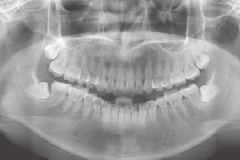

早期矫正

儿童优选 · 专为3~12岁儿童设计

量身定制 · 针对孩子不同情况定制矫正计划

正牙助萌 · 同步完成获得理想面型